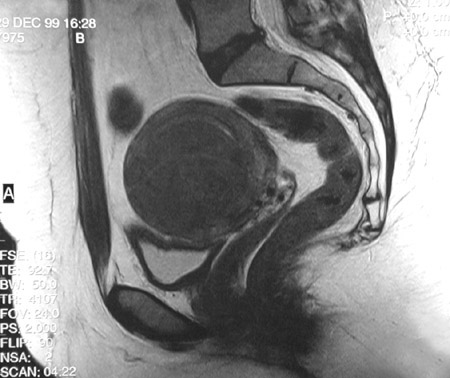

| These fast spin echo T2 weighted MRI scans of the pelvis in sagittal view above and axial view below reveal a large mass arising in the region of the uterus. The rectum, the vagina, and the bladder are also seen. A leiomyosarcoma is most likely to be a large, solitary mass, but they are far less common than leiomyomas. Leiomyosarcomas do not arise from leiomyomas. The biologic behavior of leiomyosarcomas can be unpredictable. |